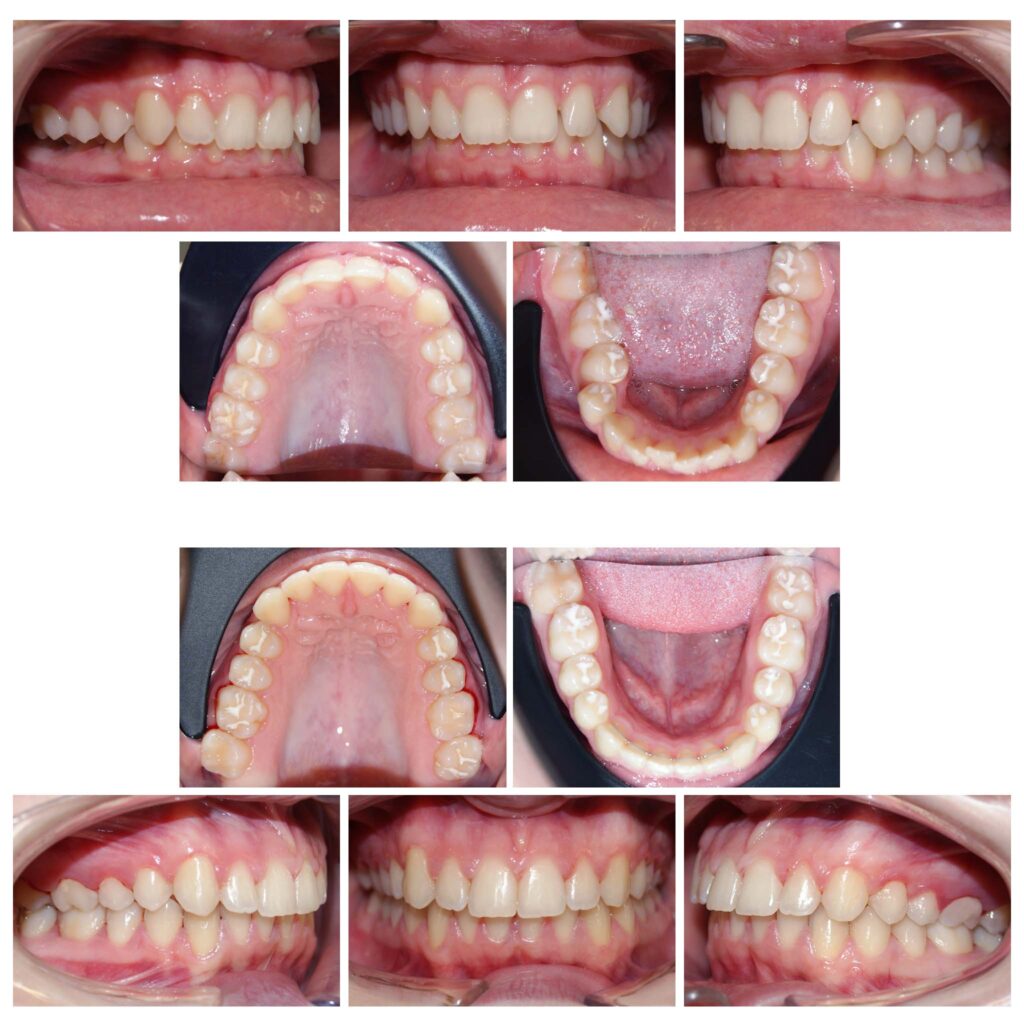

Îndreptarea axelor dentare are un efect semnificativ atât asupra dinților cât și asupra țesuturilor de susținere